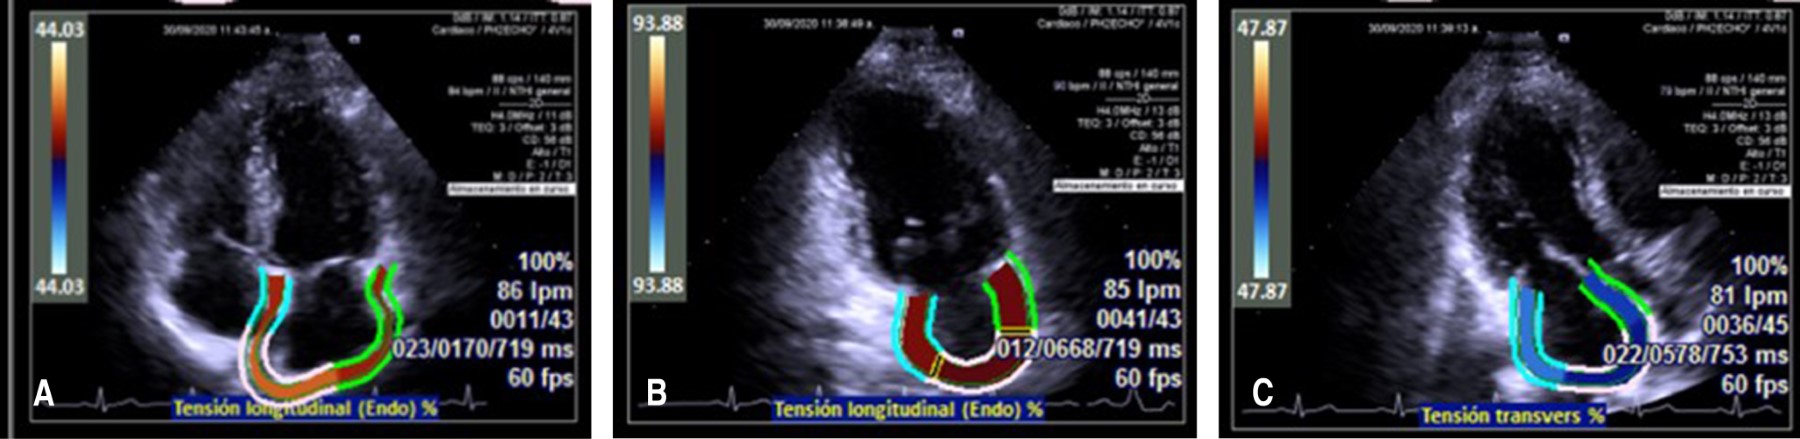

El strain de aurícula izquierda evaluado mediante ecocardiografía bidimensional con speckle tracking se ha convertido en una importante parte de la evaluación de la función auricular en diferentes patologías. El objetivo fue comparar el porcentaje de deformación miocárdica de la aurícula izquierda evaluado mediante medición monoplanar, biplanar y triplanar. El estudio fue transversal, prospectivo, observacional, analítico y unicéntrico, la deformación auricular fue evaluada utilizando la deformación de la aurícula izquierda, se obtuvo utilizando el software syngo® Velocity Vector Imaging technology. Se determinó utilizar la vista apical 4, 2 y 3 cámaras para poder calcular la deformación miocárdica. Pacientes mayores de 18 sin factores de riesgo cardiovascular sin enfermedades previas crónicas, infecciosas o congénitas fueron incluidos. Se recabaron en total 126 pacientes sanos, de los cuales 71 (56%) eran del género masculino, la media de edad de la población fue de 38 años (± 16). La variabilidad intraobservador e interobservador fue adecuada. Se compararon los diferentes valores de la aurícula izquierda, en el strain reservorio, sólo se encontró diferencia significativa entre los valores de apical 3 cámaras y el apical 2 cámaras; en el strain bomba no hubo diferencias significativas en los valores; en el strain conducto nuevamente la vista apical 3c fue la menor, encontrando diferencia significativa con el apical 4c, apical 2c y biplanar. Se relacionó la concordancia del strain reservorio de cada vista apical de manera independiente con biplanar y triplanar, documentando que tanto la vista apical 2c y la apical 4c tenían buena concordancia con ambas vistas, sin embargo, la vista apical 3c tenía una menor concordancia. Lo mismo se encontró en el strain bomba y el strain conducto. Siendo superiores las vistas apicales 2c y 4c. Conclusión: La vista de tres cámaras tiene resultados diferentes a las demás vistas y la concordancia de todos los demás valores de la aurícula izquierda es similar, por lo que no le da más valor tomarlo en biplano o triplano. Con base en la información obtenida no se debe utilizar la vista de tres cámaras y se puede utilizar una evaluación monoplanar, ya sea 4 o 2 cámaras con concordancia similar.

Figura 1